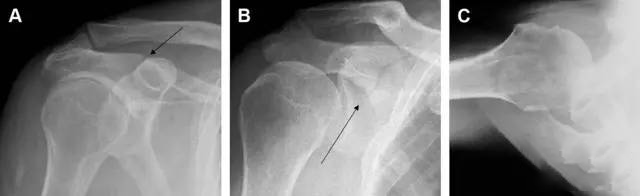

图 肩胛骨骨折正侧位片:由于骨块的叠加,(A)前后位片示「V」形高密度影(*),肩胛颈下方可见骨皮质碎片(箭头);(B)侧位片示骨皮质中断,骨折段移位,但由于肱骨的重叠遮挡,决断往往比较困难